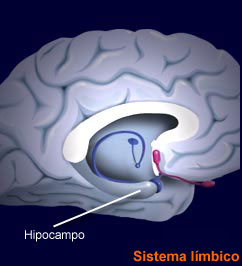

Esta supercentral hormonal cumple unas funciones determinantes en el ser humano. Louann Brizendine, la autora revelación sobre el cerebro femenino, sitúa la glándula pituitaria como sexta estructura que lo caracteriza: “produce las hormonas de la fertilidad, producción de leche y comportamiento de crianza. Ayuda a poner en marcha el cerebro maternal”. Además, en el salto de la pubertad se desencadena la propulsión de las células hipotalámicas y la niña-mujer comienza a experimentar cambios que ya se repetirán día a día, mes a mes hasta la menopausia, porque “la glándula pituitaria… salta a la vida cuando los frenos químicos se sueltan en las células hipotalámicas […]. Esta liberación celular dispara el sistema hipotalámico-pituitario-ovárico” (1). El conocimiento de esta realidad recurrente en la vida de la mujer debe ayudar a los hombres a respetar íntegramente estos ciclos vitales que producen desajustes vitales, por responsabilidad directa de la naturaleza al estar muy desarrollada esta glándula en la mujer en el lóbulo anterior de la misma (recuerdo que el peso específico de esta zona desarrolla el 80% de su función diaria y perfectamente programada). No ocurre lo mismo en el cerebro masculino, porque el balanceo hormonal no pasa tanta factura en la vida ordinaria. Si se conoce bien esta estructura, se respeta. Además, se pueden poner ejemplos rotundos de este “conocimiento” cerebral femenino, basados en una hormona bastante desconocida a nivel popular pero que juega un papel trascendental en la mujer y en las relaciones de pareja. Me refiero a la oxitocina, una hormona muy atractiva para el objeto de estas publicaciones.

El lóbulo posterior de la glándula pituitaria es el productor por excelencia de la oxitocina, llamada también la “hormona de las relaciones”, encontrándose tanto en el hombre como en la mujer. La realidad de las relaciones a largo plazo juega una baza muy importante para el equilibrio de la oxitocina (omnipresente en la mujer) junto a la vasopresina, característica del cerebro masculino. Cuando ambas se complementan, el equilibrio emocional y sentimental de las personas que conforman una pareja liberan en momentos justos estas dos hormonas, obligatoriamente obligadas a entenderse. Una caricia a tiempo libera oxitocina en la mujer y el bienestar en ella está garantizado. Igualmente, en el cerebro masculino se libera vasopresina, como buscadora insaciable de retroalimentación. A partir de aquí la cascada de emociones es un juego reservado al conocimiento de uno mismo y de su pareja, de sus amigos. Es lo que ocurre cuando imaginamos aquello que queremos o vemos en una foto a la persona que amamos: mujer, hijos, amigos íntimos. La oxitocina está detrás. La glándula pituitaria es la responsable de este equilibrio hormonal, en el que los aprendizajes y comportamientos adquiridos “neutralizan” en muchas ocasiones la forma de ser de cada una y cada uno. Cuando la oxitocina y la vasopresina se desarrollan con la normalidad programada en el cerebro individual, la dopamina juega su papel estelar de proporcionar placer, en un triángulo amoroso descifrable: ménage à trois, que dicen en Francia.